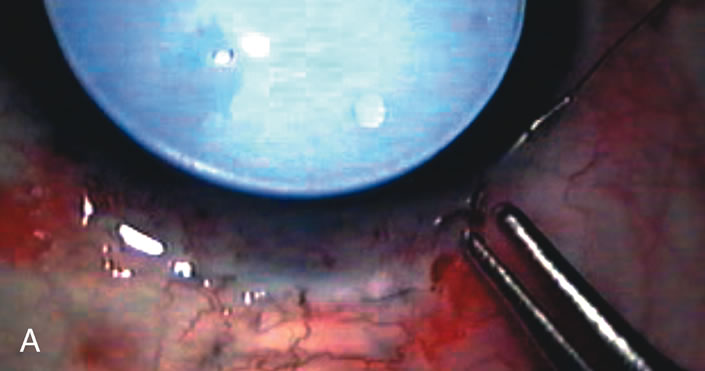

In years past, patients with both cataract and glaucoma frequently provided overwhelming surgical challenges for the ophthalmologist. The ability to carry out phacoemulsification through a 3.2-mm corneal incision along with inserting a foldable IOL is a vast improvement over 11-mm incisions that were common a decade ago (Fig. 1). The anatomical and inflammatory changes to the eye are less with small incision techniques, improving the likelihood of success with concomitant glaucoma surgery. Pharmacologic inhibition of fibrosis along with postoperative wound revision increases the long-term success rate of filtration surgery when combined with lens extraction. (Fig. 2). The learning curve may be steep at times, but the blending of cataract and glaucoma surgical skills slowly falls into place as the surgeon constantly learns and upgrades his or her technique.

Fig. 1. The anatomic advantage of small incision cataract surgery for the glaucoma patient. A. Long-term bleb function with a large cataract incision is difficult to achieve with either ECCE-trabeculectomy or trabeculectomy followed later by ECCE. This bleb failed to form sufficiently when combined with large incision ECCE. The inflammation, bleeding, and long-term wound healing with stimulation of fibroblasts associated with this technique are more likely to cause bleb failure. In addition, the increased iris manipulation necessary to deliver the nucleus and subsequent iris repair adds to the long-term breakdown of the blood aqueous barrier. B and C. Two-site phacotrabeculectomy has the advantage of small incision cataract surgery combined with separate site trabeculectomy. The incision size is one third the size of the standard ECCE. The inflammation is less severe, and cataract wound healing is confined to the temporal area. Visual rehabilitation with phacoemulsification and foldable IOL is much faster. Phacoemulsification allows successful lens extraction even in the unfriendly environment of a smaller pupil compared with ECCE. The trabeculectomy is performed in an entirely different site, well away from the wound healing associated with temporal phacoemulsification. The likelihood of this filter functioning long-term is greater than with ECCE-trabeculectomy. D. The surgeon also has the option of single-site phacotrabeculectomy with foldable IOL. Both the lens extraction and trabeculectomy are performed through one small 3.5-mm limbal incision.